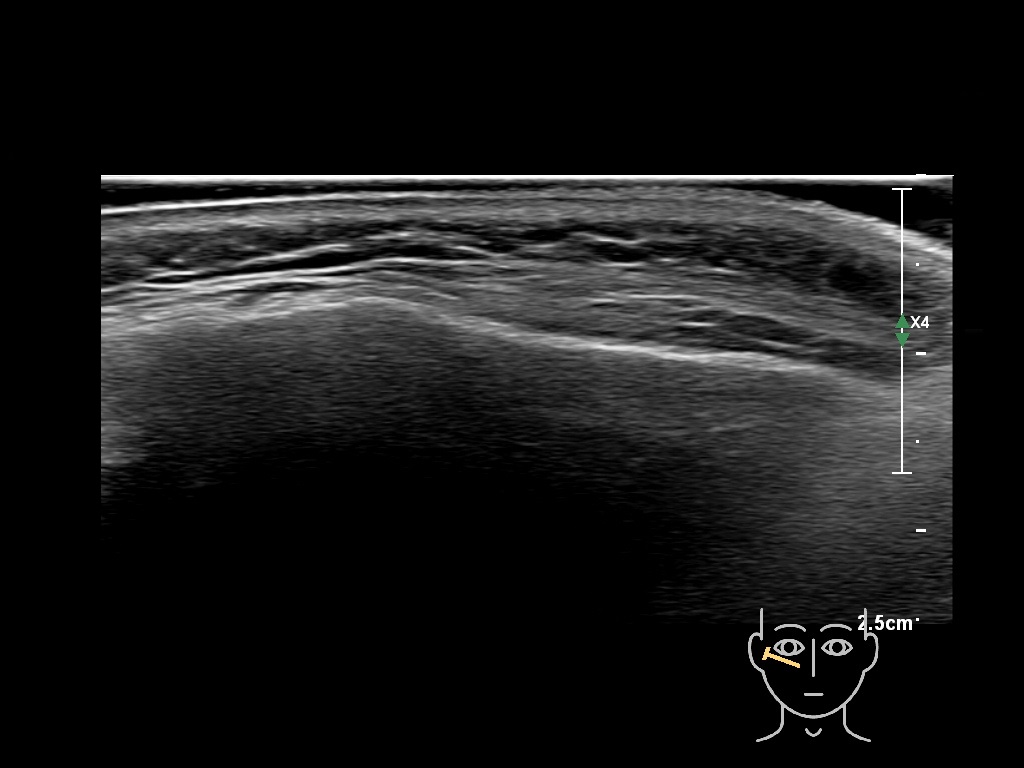

Draw in the image on the right where the fillers are located. To check if your answer is correct, please click on the secondary image.

Draw in the second image below where the fillers are located. To check if your answer is correct, swipe the first image to the right.